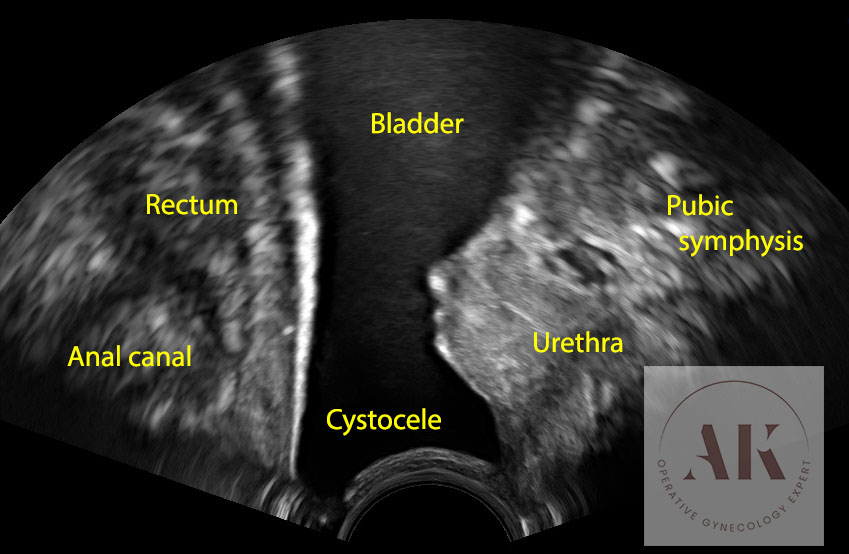

Στην πρόπτωση κύστης ή αλλιώς κυστεοκήλη, η ουροδόχος κύστη δεν αδειάζει πάντοτε όπως πρέπει, με αποτέλεσμα να δημιουργείται συνεχώς ένας μικρός υπολειπόμενος όγκος ούρων. Αυτό αποτελεί από μόνο του κίνδυνο για συχνές ουρολοιμώξεις.